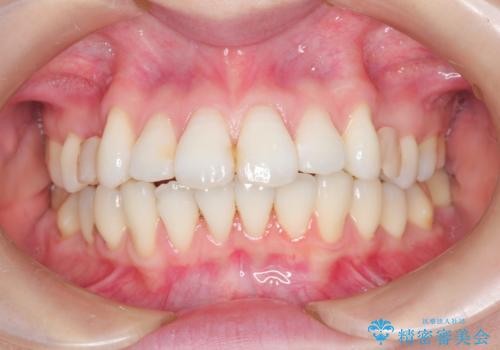

裏側のワイヤー矯正 抜歯して前歯をしっかり後ろに下げる

- 出っ歯が気になるとのことで来院されました。

上顎の、前から4番目の歯を左右1本ずつ抜歯して前歯を後方に下げる計画としました。

目立たずに矯正をご希望でしたので、裏側矯正で治療を行いました。

上下裏側矯正であったため、舌に傷や口内炎ができるなどつらい経験もされましたが、目立たずに治療できたことに喜んでいただけました。